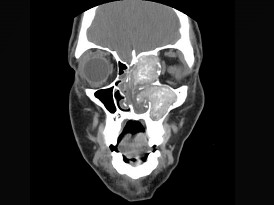

15.17歲男性,左側上瞼下垂,CT檢查如圖所示,請選擇正確的描述或診斷  (    )

正確答案:ABCD